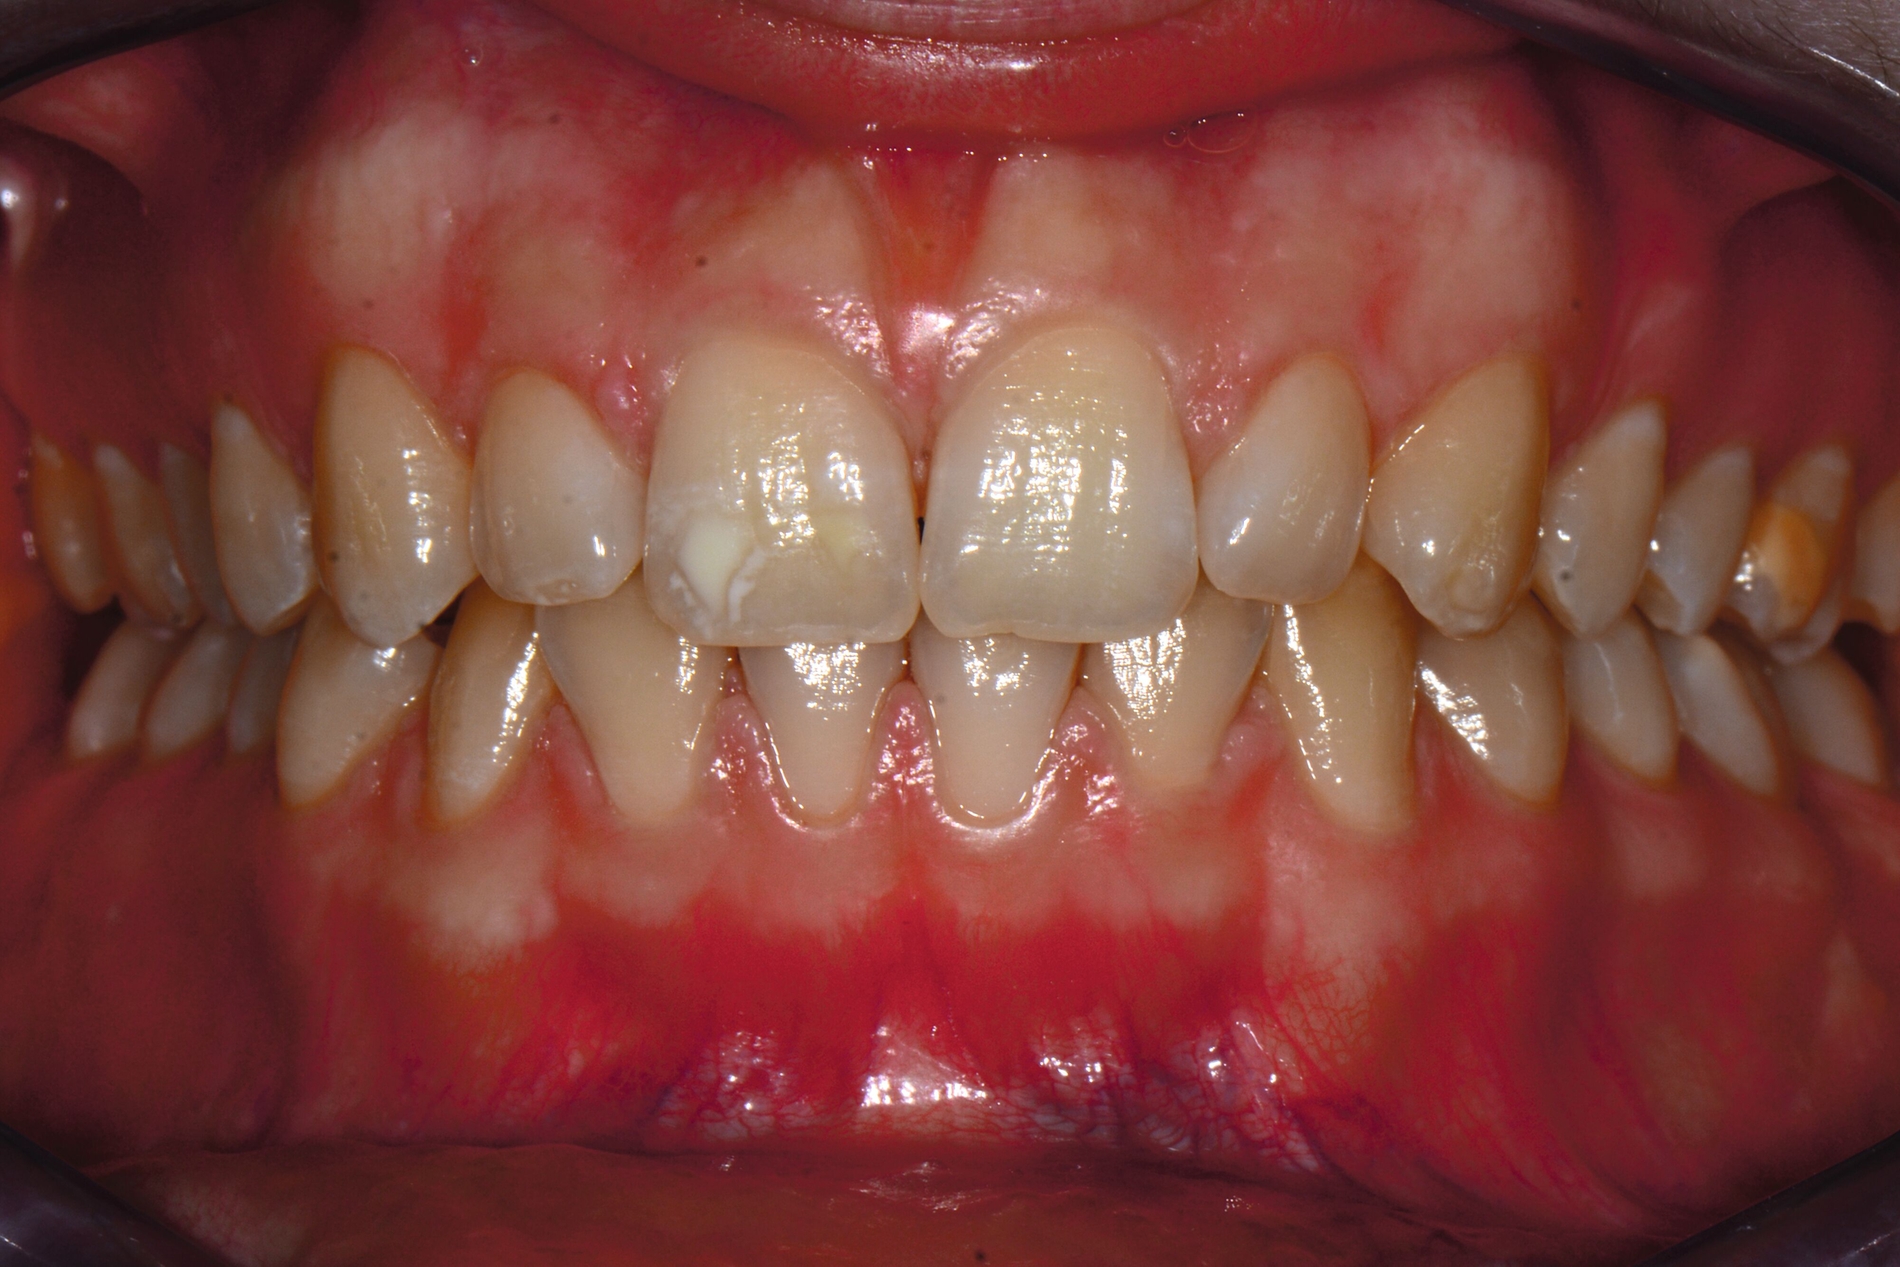

Das klinische Erscheinungsbild an bleibenden Zähnen zeigt typischerweise weißlich-gelbe bis gelblich-braune Opazitäten, die zumindest in einigen Bereichen durch eine scharfe Abgrenzung (engl.:„demarcated opacities“) zum gesunden Zahnschmelz charakterisiert sind (Abbildungen 3 und 4). Die abgegrenzten Hypomineralisationen befinden sich mehrheitlich im Bereich der inzisalen Kronenhälfte unabhängig von dem Auftreten an Front- oder Seitenzähnen. Die Ausprägung am Zahn kann dabei auf einzelne Areale oder Höcker begrenzt sein.

Frontzähne sind seltener von MIH-bedingten Schmelzeinbrüchen und Hypersensitivitäten betroffen. Von den posteruptiven Oberflächeneinbrüchen sind präeruptive Defekte abzugrenzen. Diese Zähne brechen bereits mit einem vorhandenen Oberflächendefekt in die Mundhöhle durch.

Die häufigste und relevanteste Differenzialdiagnose sind kariöse Läsionen. Dies trifft vor allem für kariesaktive Patienten zu, die multiple und ausgedehnte (initial)kariöse Läsionen aufweisen können. Die Differenzialdiagnostik gelingt hier auf Grundlage einer sorgfältigen klinischen Untersuchung, wobei die Lokalisation und Konfiguration wichtige diagnostische Hinweise geben. Kariöse Läsionen sind dabei typischerweise im Bereich von Plaqueretentionsstellen, zum Beispiel Gingivarand und Approximalflächen, detektierbar. Demgegenüber befinden sich Hypomineralisationen mehrheitlich im Bereich der inzisalen Kronenhälfte und damit außerhalb der Kariesprädilektionsstellen.

Eine weitere Strukturstörung ist die Dentalfluorose. Das klinische Erscheinungsbild von Fluorosen unterscheidet sich durch diffuse Opazitäten grundlegend im Vergleich zu den scharf begrenzten Opazitäten der MIH-Zähne. Fluorosen treten symmetrisch und möglicherweise an allen Zähnen infolge einer langfristigen Fluoridüberdosierung auf. Genetisch bedingte Erkrankungen der Zähne, wie Amelogenesis imperfecta und Dentinogenesis imperfecta, werden durch spezifische Genmutationen verursacht und sind dadurch gekennzeichnet, dass alle Zähne beider Dentitionen gleichermaßen betroffen sind [Kühnisch et al., 2025; DGKIZ et al., 2024]. Im Gegensatz dazu sind MIH-Defekte mehrheitlich an den sogenannten Indexzähnen zu finden. Zudem ist oftmals ein symmetrisches Auftreten zu beobachten.